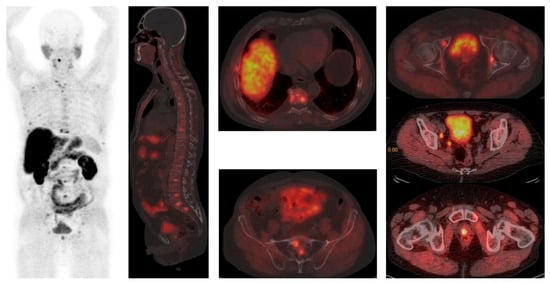

Current Status and Future Perspectives of Nuclear Medicine in Prostate Cancer from Imaging to Therapy: A Comprehensive Review

Nuclear medicine has emerged as a critical modality in the diagnostic and therapeutic management of urological malignancies, particularly prostate cancer. Advances in single-photon emission computed tomography/computed tomography (CT) and positron emission tomography/CT (PET/CT) have enhanced tumor assessment across staging, treatment response, and recurrence settings. Molecular imaging, which offers insights beyond traditional anatomical imaging, is increasingly integral in specific clinical scenarios. Theranostic nuclear medicine, which combines diagnostic imaging with targeted therapy, has become a well-established treatment option, particularly for patients with metastatic castration-resistant prostate cancer (mCRPC). The development of the prostate-specific membrane antigen (PSMA) radioligands has revolutionized clinical management by enabling precise disease staging and delivering effective radioligand therapy (RLT). Ongoing research aims to refine the role of PSMA PET imaging in staging and treatment monitoring, while optimizing PSMA-targeted RLT for broader clinical use. Given that prostate cancer remains highly prevalent, the anticipated increase in the demand for RLT presents both challenges and opportunities for nuclear medicine services globally. Theranostic approaches exemplify personalized medicine by enabling the tailoring of treatments to individual tumor biology, thereby improving survival outcomes and maintaining patients’ quality of life with minimal toxicity. Although the current focus is on advanced disease, future research holds promise for expanding these strategies to earlier stages, potentially enhancing curative prospects. This evolving field not only signifies a paradigm shift in the care of prostate cancer patients but also underscores the growing importance of nuclear medicine in delivering precision oncology. Full article

Show Figures

Figure 1